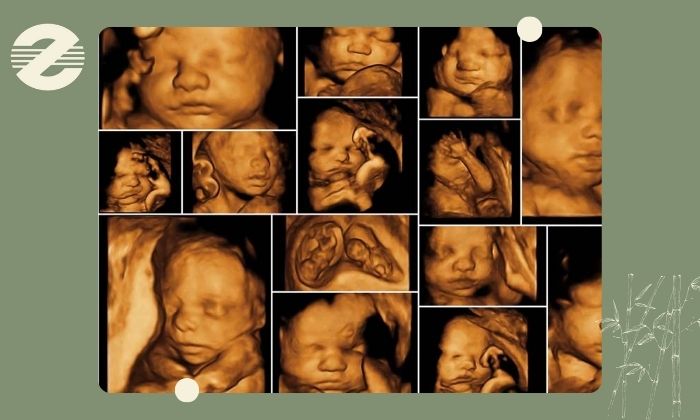

مرکز تصویربرداری پزشکی زعیم تحت مدیریت دکتر علیرضا سرزعیم (فلوشیپ مداخلهای) با همکاری دکتر سمیه زارعی و دکتر مهرناز راسته خدمات تخصصی غربالگری آنومالی جنین را را براساس جدیدترین پروتکلهای غربالگری و با بهرهگیری از فناوریهای روز ارائه میکند. این تیم با دانش بهروز در حوزه تصویربرداری پریناتال قادر است ساختارها و اندامهای جنین را بهدقت بررسی کرده، اختلالات احتمالی را در مراحل حساس بارداری شناسایی نماید و گزارشهایی جامع و کاربردی را در اختیار پزشک و مادر قرار دهد.تجهیزات پیشرفته مرکز

در این مرکز دستگاههای نسل جدید سونوگرافی مطابق استانداردهای جهانی برای بررسی ساختار اندامهای جنین مورد استفاده قرار میگیرند. این تجهیزات توانایی ارائه تصاویر با وضوح بسیار بالا را دارند و امکان تشخیص دقیق ناهنجاریهای استخوانی، قلبی، مغزی و دیگر اندامهای جنین را فراهم میسازند.اطلاعات جمعآوری شده توسط تیم پزشکی مرکز به صورت تخصصی بررسی و گزارش میشوند تا روند تصمیمگیری و اقدامات پزشکی با اطمینان کامل انجام گیرد.